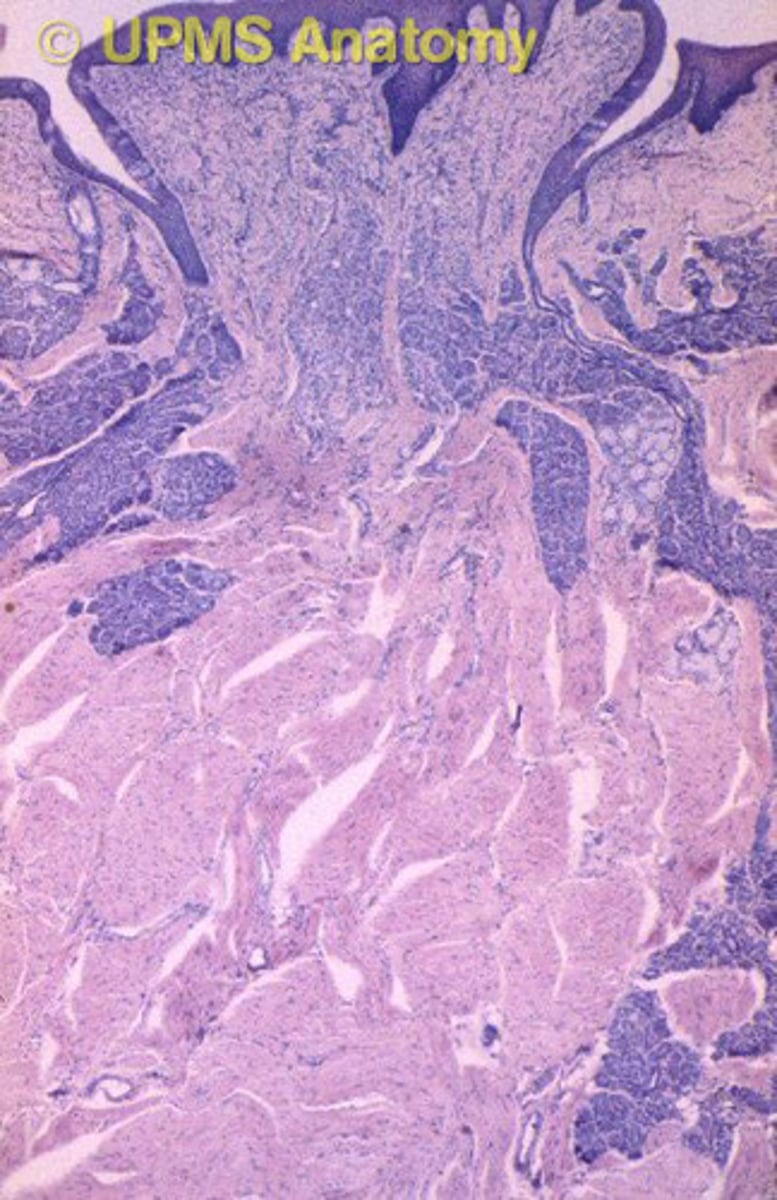

Beskriv Papilla vallatae

- Specialiserad mucosa som finns på tungan och bidrar till smaksinnet

- Smaklökarna sitter på papillans sida i vallgravarna

- Sidorna är inte keratiniserade men toppen är det

Vad finns vid papilla vallate, funktion?

von Ebners salivkörtlar som tömmer sig i vallgravarna i syfta att spola rent så att vi ska kunna känna ny smak på bästa sätt - viktigt för smakupplevelsen